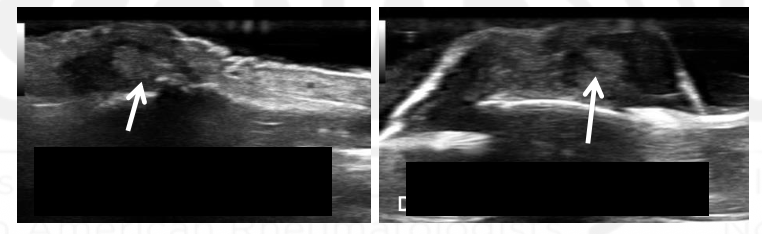

What view is this?

Extensor Tendon

Digital Vessel

Tophus

This is gouty extensor tendinopathy at the PIP.